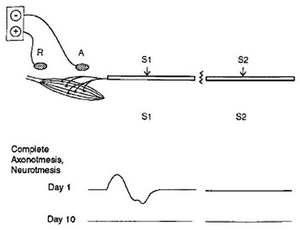

<請了解: 小腿神經手術手術後一定會無力, 然後至少一年過程逐漸恢復. 恢復期都可以藉由正常作息與手術後教導的原則幫助無力感復原. 不過, 任何神經手術都有不可逆影響, 也就是未來一定可以正常活動, 但是無法恢復到可以競賽的程度, 或多或少長期都有輕微無力感. 這是任何蘿蔔腿手術只要有效, 都要面臨的代價>

對小腿肌肉外形想要改善, 斧底抽薪的做法是將最激突的部位弄瘦, 即把gastrocnemius肌肉的神經讓它失去作用, 一般這種"去神經化的肌肉萎縮" (denervation muscle atrophy), 當支配與控制此一肌肉的神經無法再提供肌肉收縮的訊號時, 肌肉便會不再動作, 造成越來越萎縮. 大家可以想像, 如果妳一直躺在床上都不動(immobilization), 肌肉會因為消耗能量, 而使肌肉力量先變弱的症狀(muscle weakness), 再逐漸連肌肉主體都代謝掉, 被脂肪所部份取代, 所以可以看見腿的體積變小.

(3) 開刀方法: 運用顯微技術, 將內側腓腸肌(gastrocnemius m.) 的神經與比目魚肌(soleus m.)的部分神經移除, 肌肉在3到6個月內, 自然[永久]慢慢縮小, 不會像肉毒桿菌需要反覆施打.

CMAP .

CMAP .

(6) 可能後遺症: 肌肉或神經酸痛, 前三週較無力, 但不影響正常功能-- 一定要有心理準備喔!! 但是, 無力越久, 瘦得越多, 無力一停止, 就是您最後腿圍. (因為 gastrocnemius(腓腸肌)並非主要肌肉, 是輔助角色).